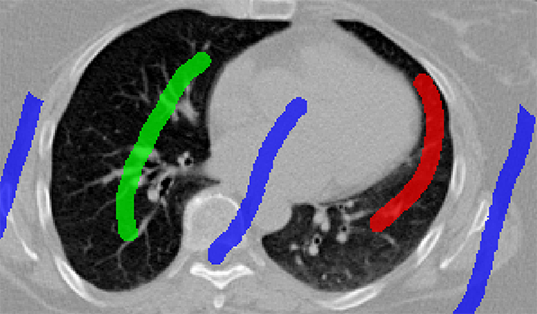

![]() |

| (a) initial seeds | (b) Potts model |

| (c) Potts model | (d) Hedgehogs + Potts |

| (c) Multi-Star + Potts model | (d) Hedgehogs + Potts model |

For the example shown in Fig.9(a), (b-c) show Potts model results for and 6, respectively. It should be noted that is the smallest smoothness weight that did not result in over-segmentation when using Potts. However, the result in Fig.9(c) is biased towards smaller objects (notice star tips) because by increasing the smoothness weight we are also increasing the shrinking bias. Over-segmented results as the one in Fig.9(b) could be avoided without increasing the shrinking bias, simply by incorporating multi-shape priors. Our method which incorporates Hedgehogs shape priors with Potts model was able to find a better segmentation, see Fig.9(d).

The objective of the example shown in Fig.10(a) is to segment left and right lungs, and the background. Potts model result shown in Fig.10(b) has holes, i.e. part of the background appears in the middle of the lungs. Furthermore, Potts model converged to biased color models where the right lung preferred brighter colors while the left preferred darker colors. Similar to the previous example, increasing for Potts model will increase the shrinking bias and it becomes hard to segment the elongated part of the the right lung. Using multi-star which is a generalization of [25] to multi-object segmentation is not enough because the right lung is not a star-shape. To be specific, there is no point inside the right lung that could act as a center of a star-shape that would include it. Fig.10(d) shows the result for our method, where user scribbles were used to enforce shape constraints compared to using a single pixel per label [9].